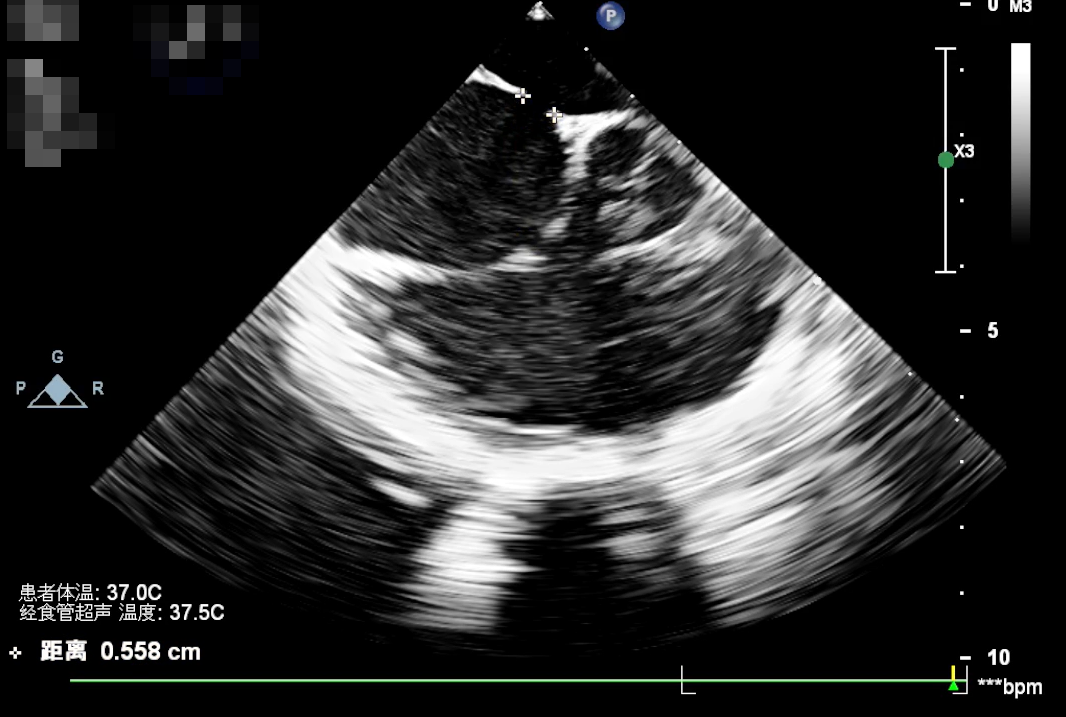

术中选伞策略:入院后术前测量剑下双房切面断距约7.7mm,术中TEE实测房间隔缺损大小为5.58mm,最终决定选择使用BDASD-Ⅱ 12封堵器,12F可降解封堵器介入输送系统进行封堵,手术通过TEE引导进行。

术中TEE实测房间隔缺损大小为 5.58mm